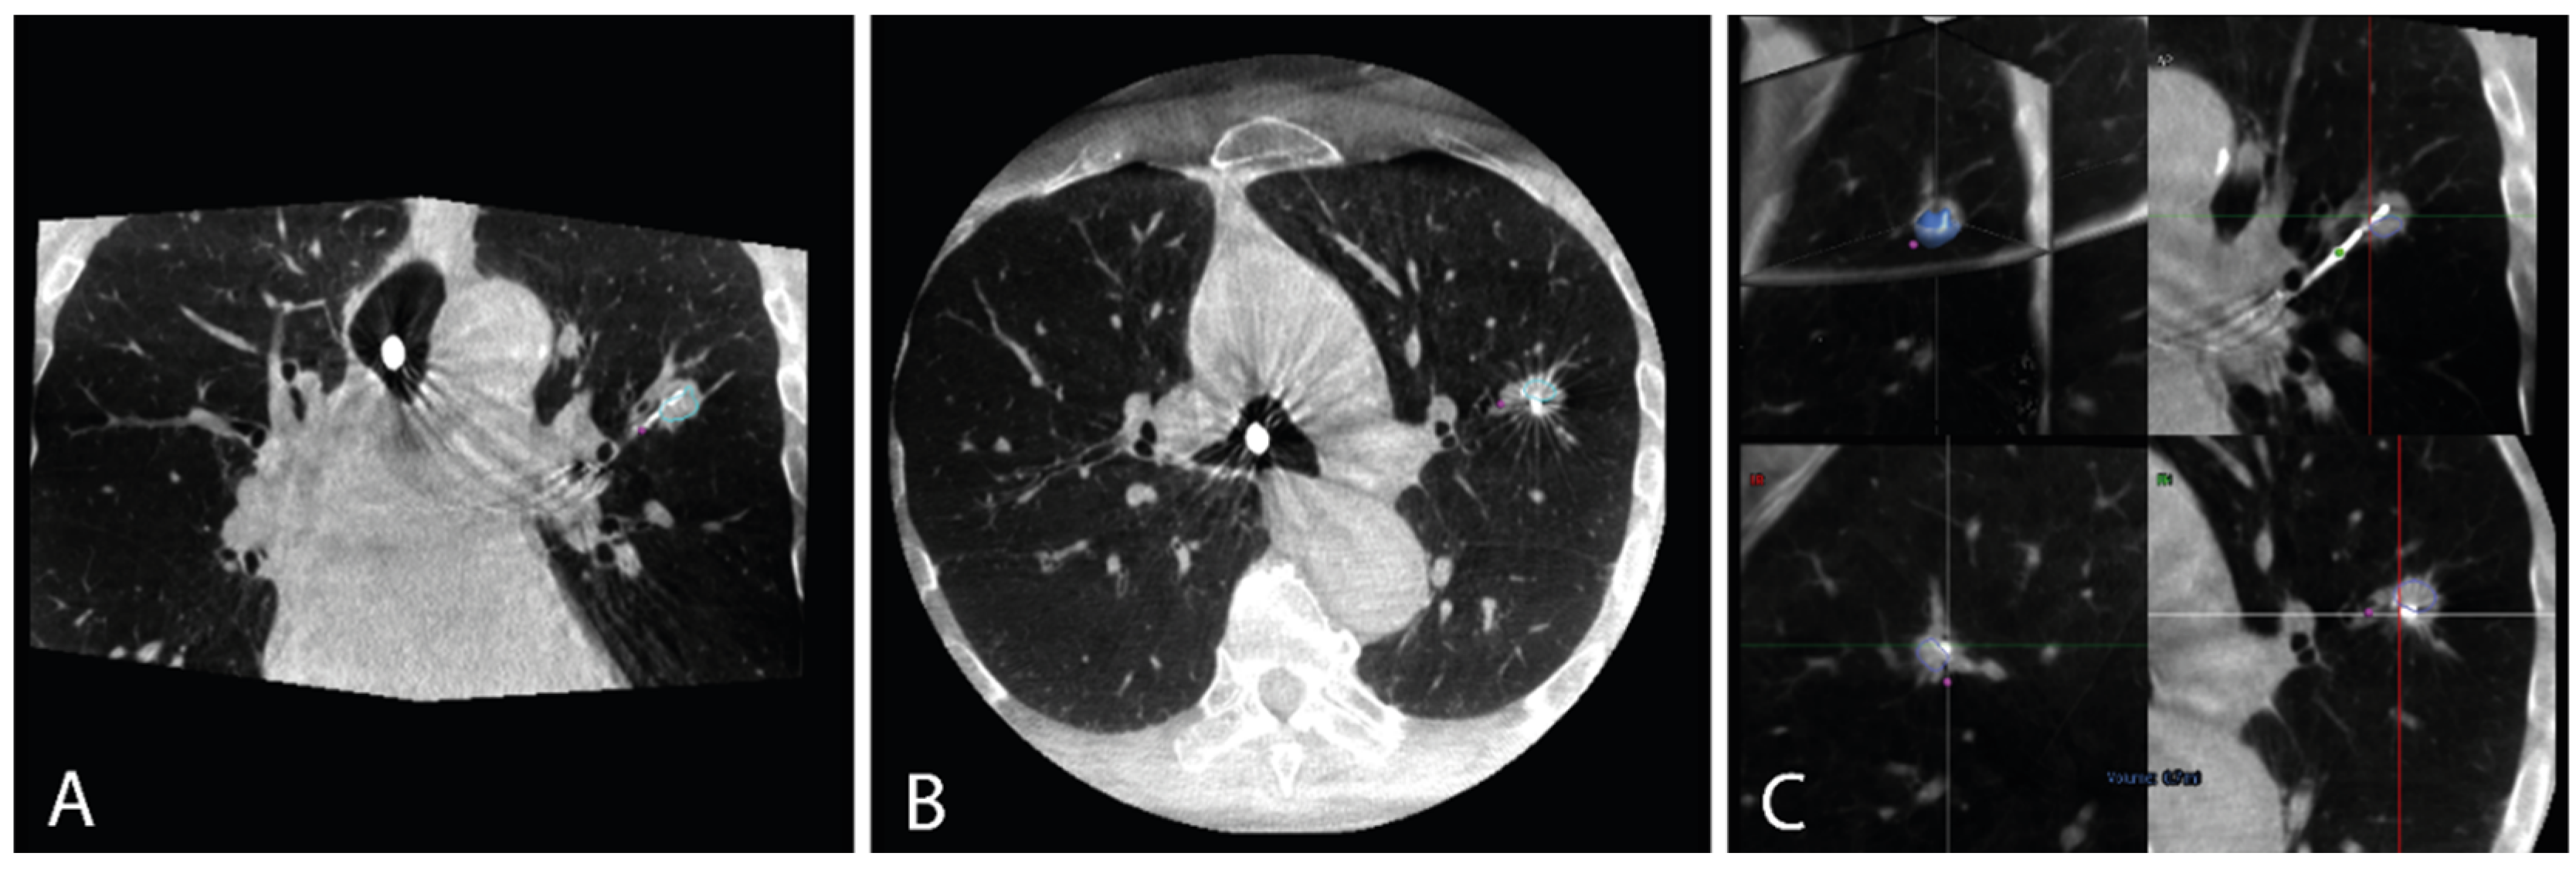

2.3.1. Pioneer Plus Radial Ultrasound

3.1. Pioneer Plus Radial Ultrasound

| Tumor visibility on radial US imaging, n (%) | 29 (96.7%) | ||

| Real-time radial US visibility of tracer injection, n (%) | 0 (0.0%) | ||